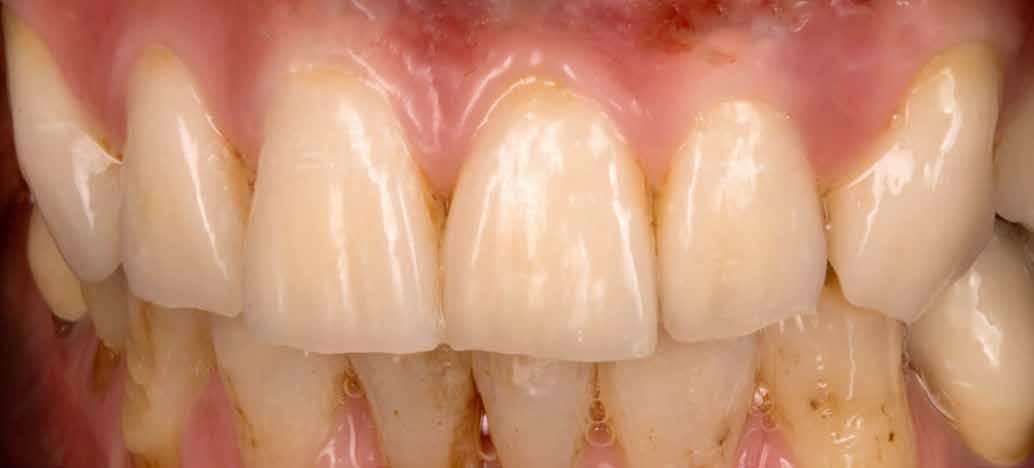

Behelyezés a rendelőben

Amint megérkezett a végleges pótlás a laboratóriumból a rendelőbe, a stégek felkerültek az implantátumokra (72–73. képek). Ketac Zem-mel ragasztották be őket. Ezt követően kerültek szájba a kivehető fogsorok, még egyszer optikailag ellenőrizve a korrekt illeszkedést. Jó látni, milyen harmonikusan illeszkedik a természetes környezetbe minden. A front optimalizált esztétikája is jól érvényesül (74–81. képek). A tökéletes illeszkedést végül röntgenképpel is ellenőrizték (82.kép).